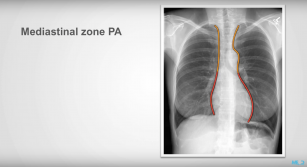

Radiological zones—an introduction to landmarks 10th Jan 2018 - Julian Dobranowski, MD, FRCPC Learn how to identify the major anatomical regions on a chest X-ray.